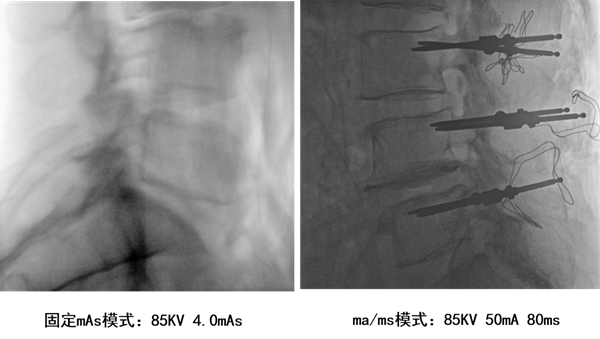

近年,安健科技发布了动态平板C臂悦画,悦画是业内首款能实现自主曝光的低剂量C臂,其ma/ms自主曝光功能根据不同手术部位、不同体型自主适配参数,在合适的厚度体层适配最佳曝光参数,从而达到“更好影像、更低剂量”的效果,让诊断需求与保护医生患者两不误。而固定mAs模式,遇到体层较厚的患者时,必须要提升剂量才能获得较好的图像质量,较难兼顾最佳图像与最低剂量的平衡;同时,悦画搭载了业界领先的CMOS平板探测器,像素高达200万,最高空间分辨率高达3.2lp/mm,微小解剖结构清晰可见,图像细节丰富,最小可见0.4mm的骨纹理间距,并且支持多级视野放大功能,方便医生诊断查看。超清的图像显示,有利于医生查看患者术前骨折状况,骨纹理,同时在术中确保钢钉和螺纹钉植入正确的位置,并且方便术后恢复情况观察。